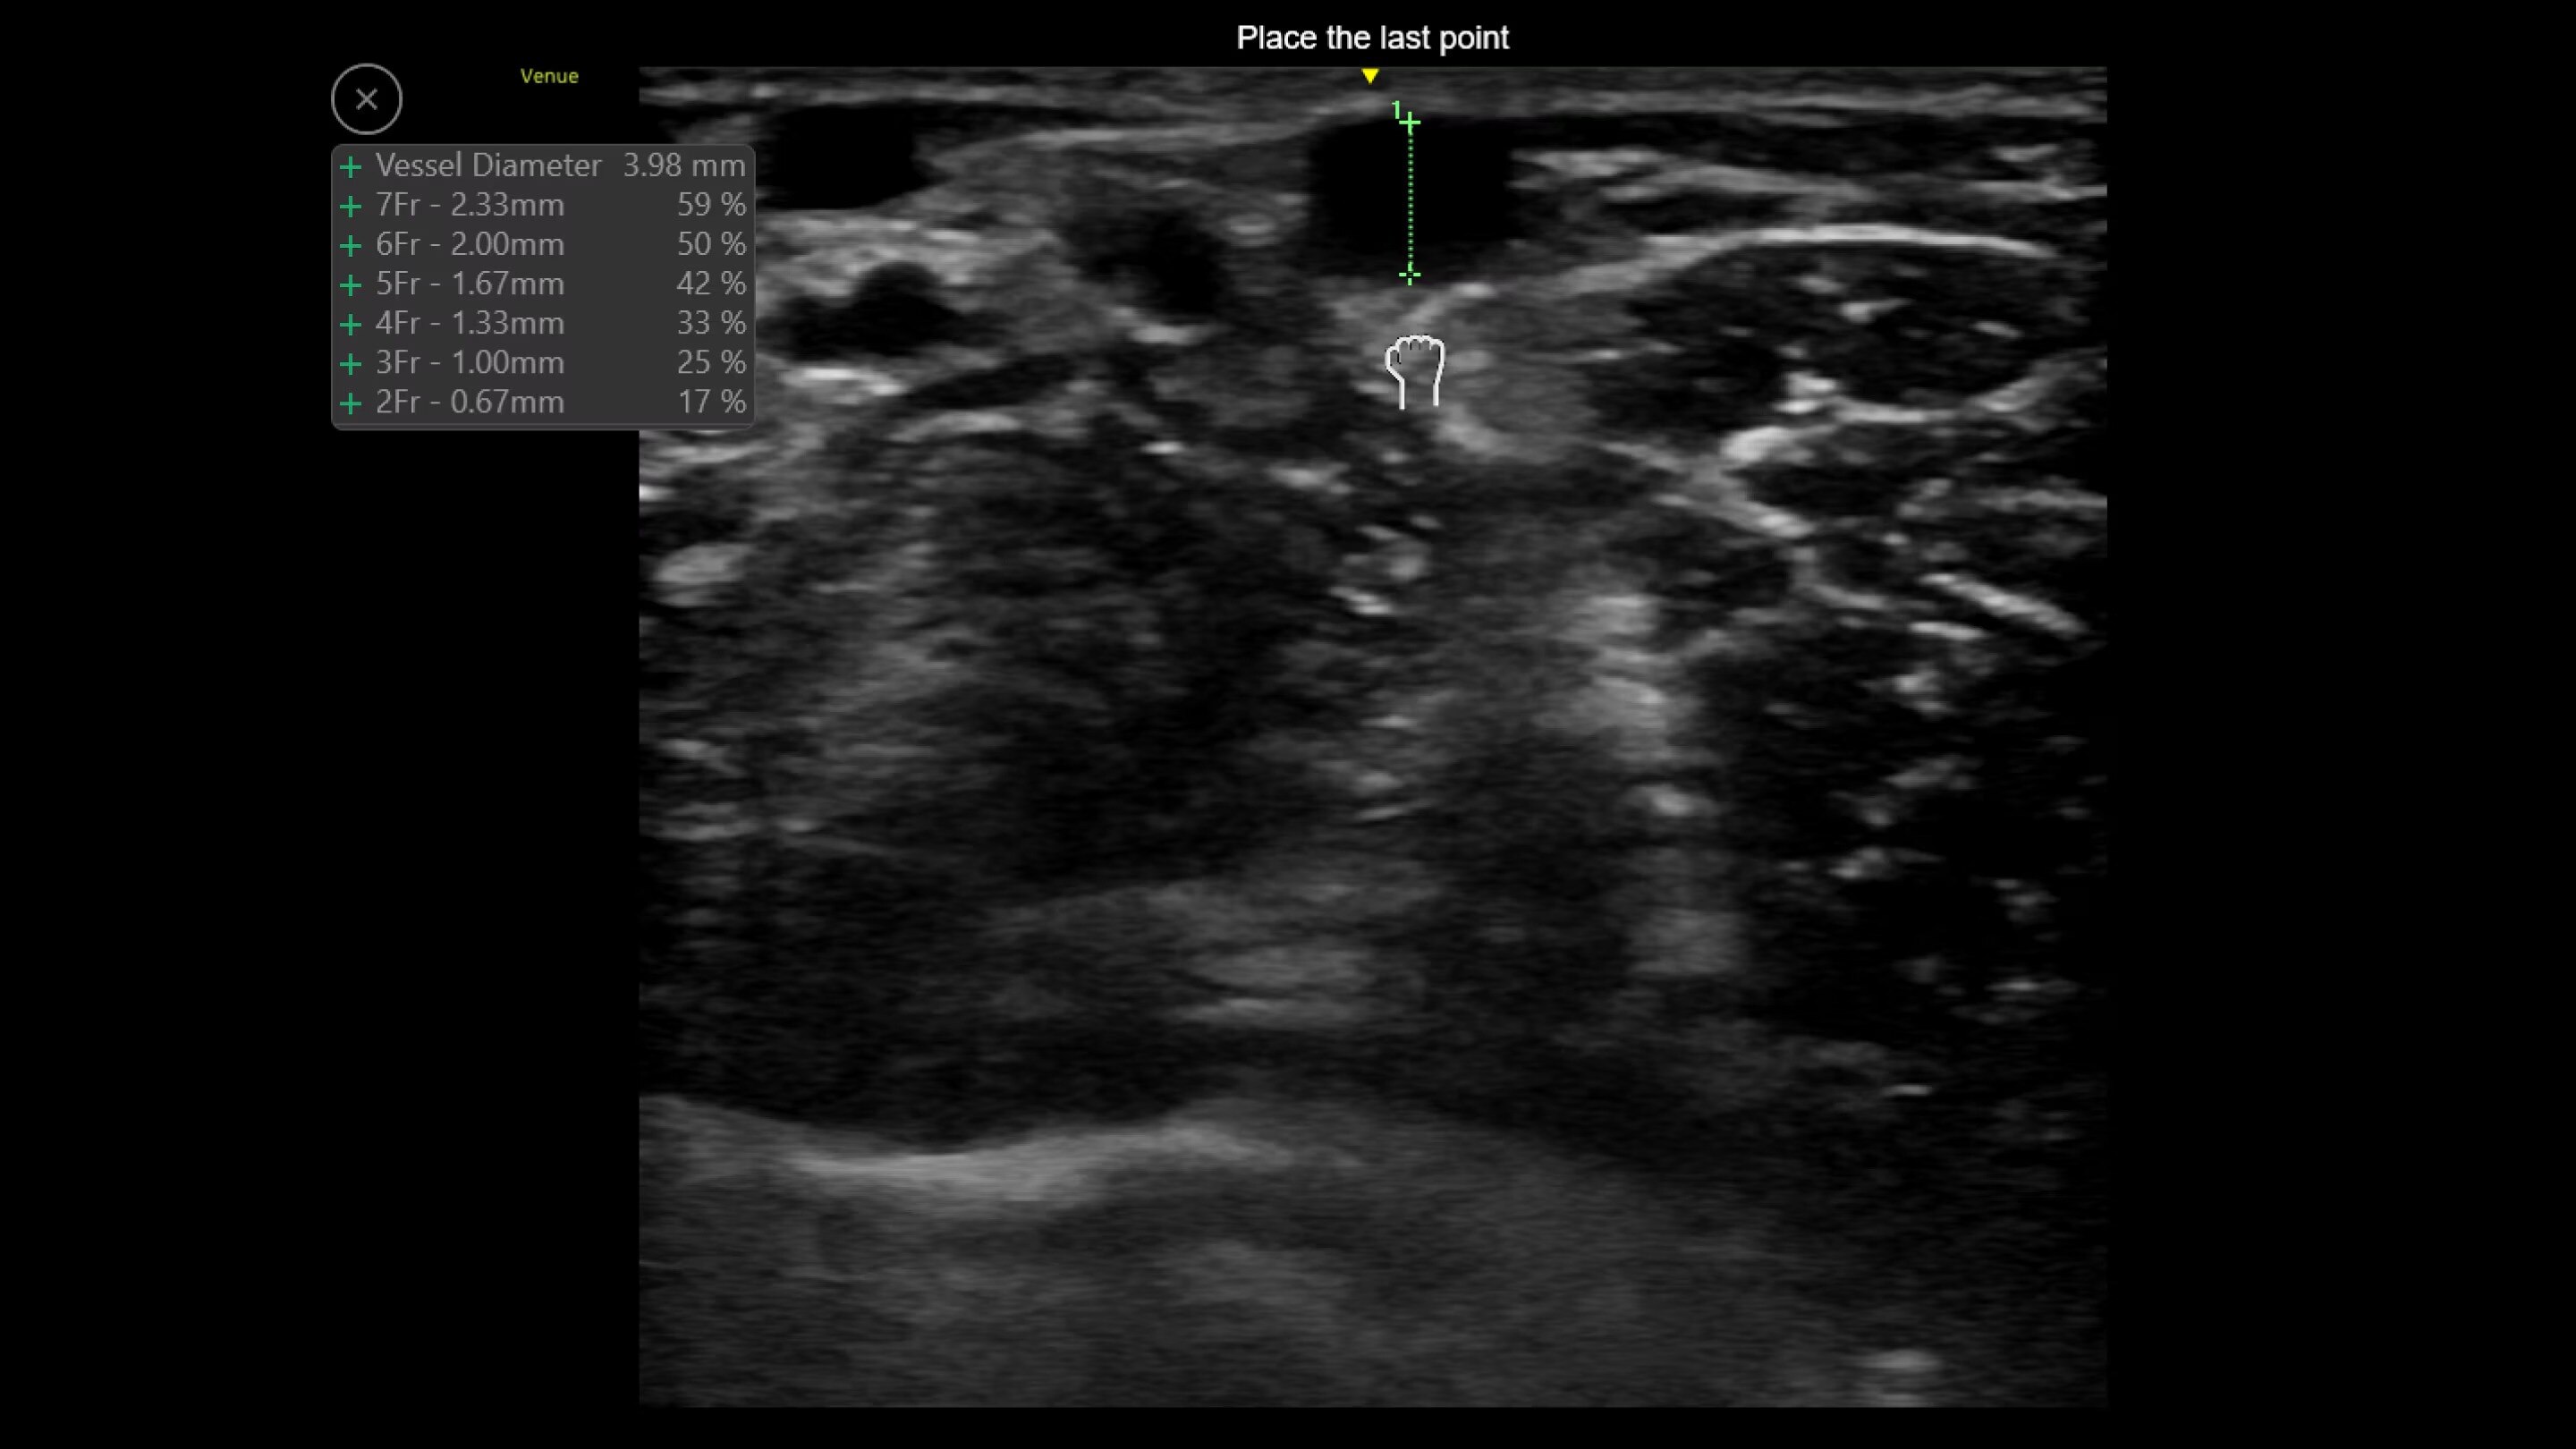

Catheter to Vessel Ratio

Accurate catheter selection tool

Selecting the wrong sized catheter can lead to catheter related thrombosis.3 Catheter to Vessel Ratio is a measurement tool that supports clinicians in selecting the appropriate sized catheter based on vessel diameter.